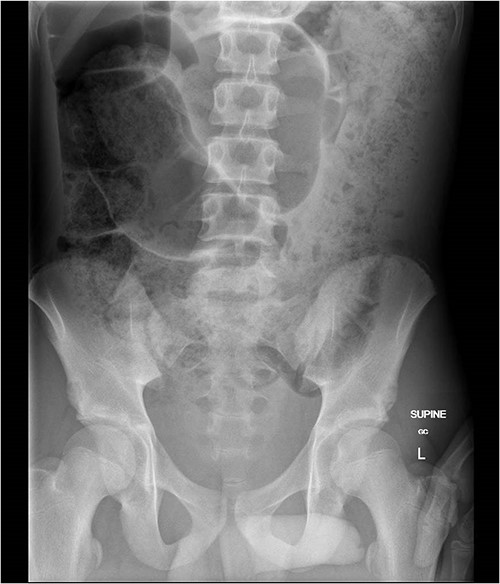

The patient presented via ambulance to a regional emergency department with diarrhoea and abdominal pain. He had a 5-day history of watery diarrhoea, intermittent cramping abdominal pain and 24 h of profuse vomiting. He had no significant medical history, developmental delay or chronic constipation. In the emergency department, the patient required methoxyflurane and multiple doses of IV morphine. He was seen by a senior paediatrician and admitted with a provisional diagnosis of bacterial gastroenteritis. Soon after admission, he became tachycardic, hypertensive and pale with a distended and hyperresonant abdomen. There was no tenderness to palpation. Plain abdominal X-ray (AXR) showed dilated loops of the large bowel (coffee-bean sign) and faecal loading throughout the ascending and descending colon suspicious for a volvulus (Fig. 1). Computed tomography (CT) demonstrated a mesenteric ‘whirl sign’ around the inferior mesenteric artery and sigmoid mesentery (Fig. 2). An emergency laparotomy revealed a sigmoid volvulus with tight twist (Fig. 3). Although viable, the sigmoid and upper rectum were resected, and a side-to-side double-stapled primary anastomosis was created. Histopathology did not demonstrate aganglionosis.

Abdominal plain X-ray demonstrated dilated loops of colon and ‘coffee-bean sign’.